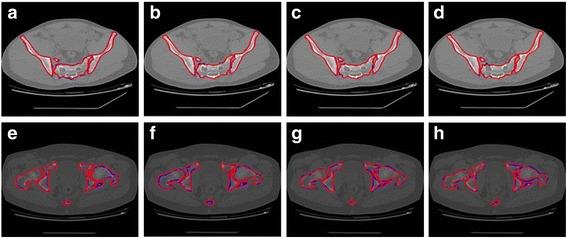

The segmentation of bones in pelvic CT images based on extraction of key frames.

The proposed method consists of two main parts: the extraction of key frames and the segmentation of pelvic CT images. Key frames were extracted based on pixel difference, mutual information and normalized correlation coefficient. In the pelvis segmentation phase, skeleton extraction from CT images and a marker-based watershed algorithm were combined to segment the pelvis. To meet the requirements of clinical application, physician's judgment is needed. Therefore the proposed methodology is semi-automated.

In this paper, 5 sets of CT data were used to test the overlapping area, and 15 CT images were used to determine the average deviation distance. The average overlapping area of the 5 sets was greater than 94%, and the minimum average deviation distance was approximately 0.58 pixels. In addition, the key frame extraction efficiency and the running time of the proposed method were evaluated on 20 sets of CT data. For each set, approximately 13% of the images were selected as key frames, and the average processing time was approximately 2 min (the time for manual marking was not included).